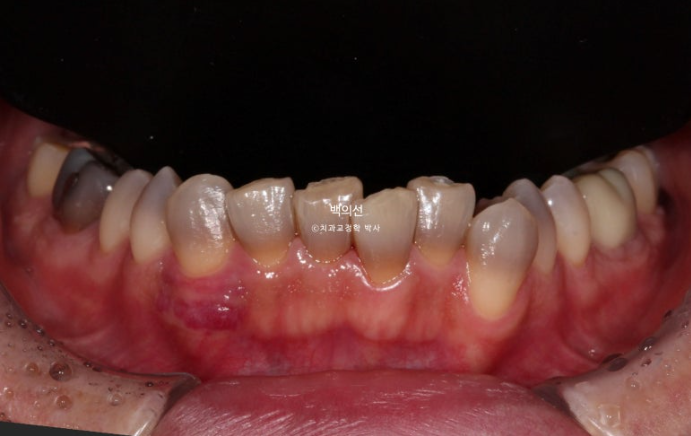

In the lower front teeth, there are varying heights in addition to the canine crowding.

The lower front teeth have stricter conditions for no-prep laminate than the upper front teeth.

Because the laminate has to wrap around the incisal edge of the lower front teeth, there needs to be some distance between the upper front teeth and the lower front teeth.

The canine crowding is fairly severe.